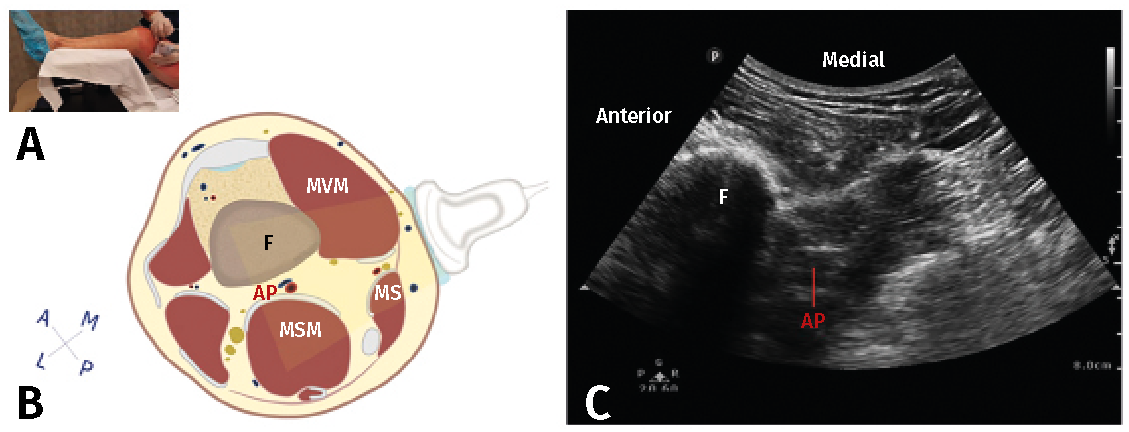

El canal de los aductores contiene, además de los vasos femorales y el nervio safeno, el nervio destinado al vasto medial, el nervio cutáneo femoral medial, el nervio retinacular medial y las ramas articulares distales del nervio obturador(4). Excepto el nervio vasto medial, el resto de los nervios son solo sensitivos y todos representan un papel importante en la inervación sensitiva de la rodilla(1). Tanto el nervio safeno como el nervio del vasto medial contribuyen a la inervación de la cara anteromedial de la rodilla y, por tanto, son dianas importantes en este bloqueo (Figura 4)(11). Dado que salen del canal de los aductores en el tercio distal, el tercio medio del canal es el sitio óptimo para la realización del bloqueo, administrando el anestésico local en ambos nervios mientras se minimiza la posibilidad de difusión proximal al triángulo femoral(12).

Figura 4. Bloqueo del canal de los aductores. A: posición del transductor al nivel del muslo; B: corte anatómico transversal del canal de los aductores; C: visión ecográfica. AF: arteria femoral; MAM: músculo aductor magno; MG: músculo gracilis; MS: músculo sartorio; MVM: músculo vasto medial; NRM: nervio retinacular medial; NSa: nervio safeno, VF: vena femoral(11).

La técnica es sencilla bajo visión ecográfica y tiene la ventaja de tener menor bloqueo motor del cuádriceps que el bloqueo del nervio femoral, aunque el uso de grandes volúmenes de anestésico local puede provocar la migración del mismo hacia porciones más proximales del nervio femoral y, secundario a ello, presentarse también bloqueo motor. En general, este bloqueo se ha popularizado en los últimos años por la menor tasa de complicaciones relacionadas con el bloqueo motor del cuádriceps, permitiendo una deambulación precoz, menor riesgo de caídas, manteniendo igualdad en la calidad analgésica y el consumo de opioides(13). La media de volumen de anestésico local utilizado es de 20 mL.